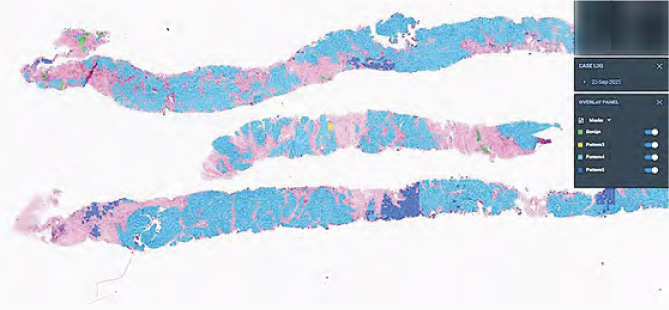

人工智能軟件可協助醫生做病理診斷,圖中是透過AI程式,將病人前列腺組織的癌細胞以藍色標示,深藍色為高度惡性。(醫管局提供)

該兩院病理學部門將化驗樣本數字病理化後,亦購入AI軟件,試行以AI輔助為乳癌及前列腺癌診斷,計劃明年2至3月開始使用,用途包括點算乳腺癌細胞,並以AI標示前列腺組織樣本病變情G。

陳昌堅說,兩院每周約有6個前列腺及10個乳癌樣本需診斷,以往病理科醫生需花時間點算癌細胞,希望AI可加快工作流程,而AI亦可於工作列表當中,優先標示患癌樣本。他說日後亦擬將AI應用於胃部、淋巴組織診斷,並自行開發AI工具。